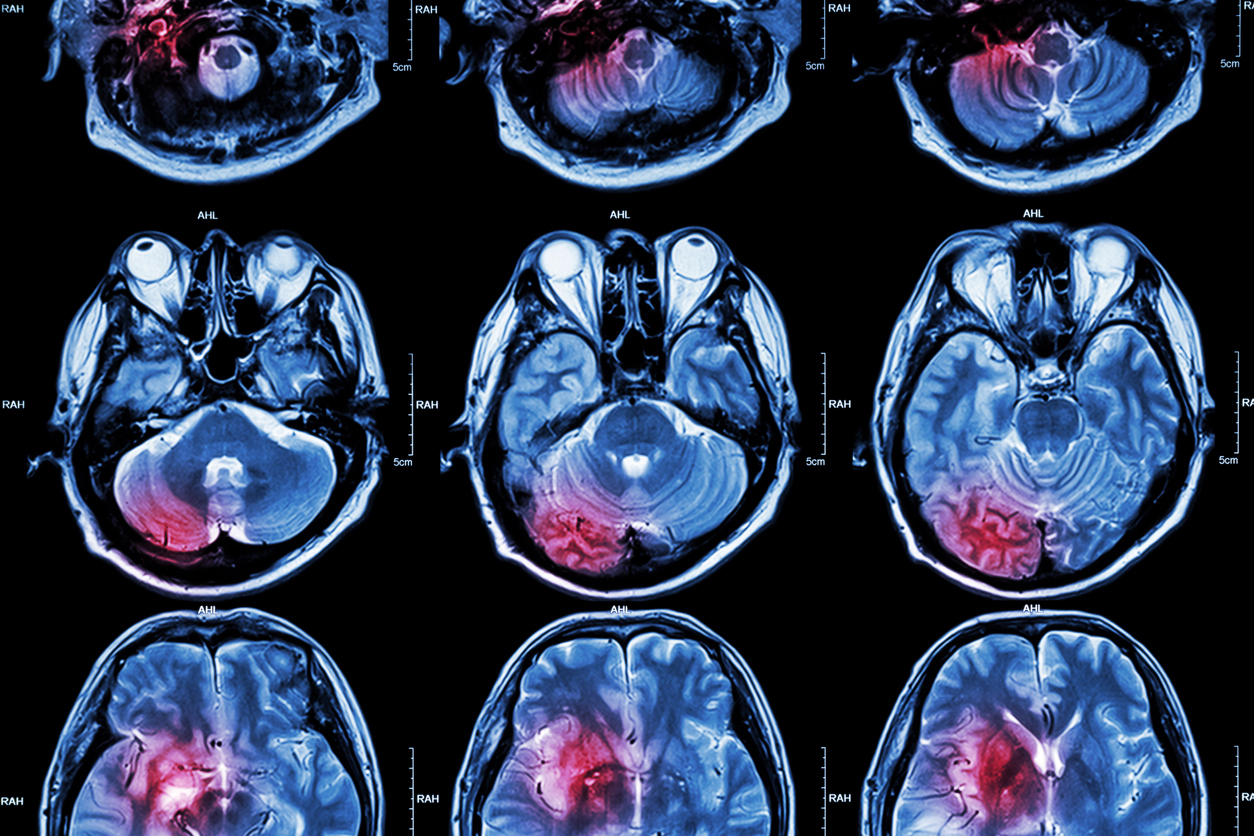

Chronic Traumatic Encephalopathy (CTE) is a progressive degenerative brain disease that has been recently linked to repeated head trauma, such as that found in contact sports like football and boxing. CTE is characterized by the accumulation of tau, a protein that normally is found in the cells of the nervous system, in brain tissue. As CTE progresses, an individual’s brain function gradually becomes impaired.

Medical researchers are attempting to better understand the pathophysiology of CTE and to find the link between the repeated head trauma and neurodegenerative changes that lead to CTE. While it was initially thought that CTE was caused by a single big hit to the head, recent research has found that repeated, lesser impacts may be more closely linked to the development of CTE.

As CTE can only be diagnosed post-mortem, there are currently no tests to diagnose CTE in living patients.